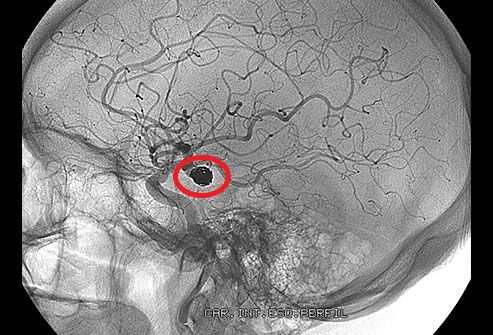

4.7 Não

Áp lực hình thành khi máu không thể lưu thông bình thường. Sự tắc nghẽn nghiêm trọng đôi khi có thể dẫn đến đột quỵ. Nếu không có oxy từ máu, các tế bào não của bạn bắt đầu chết trong vài phút. Cục máu đông trong não có thể gây đau đầu, lú lẫn, co giật, khó nói và suy nhược, đôi khi chỉ ở một bên cơ thể.